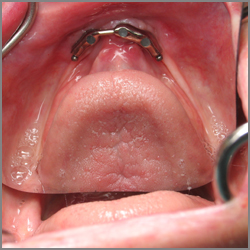

Teeth prepared for an overdenture - The denture

will fit over the metal-covered teeth that have been shaped by the

dentist.